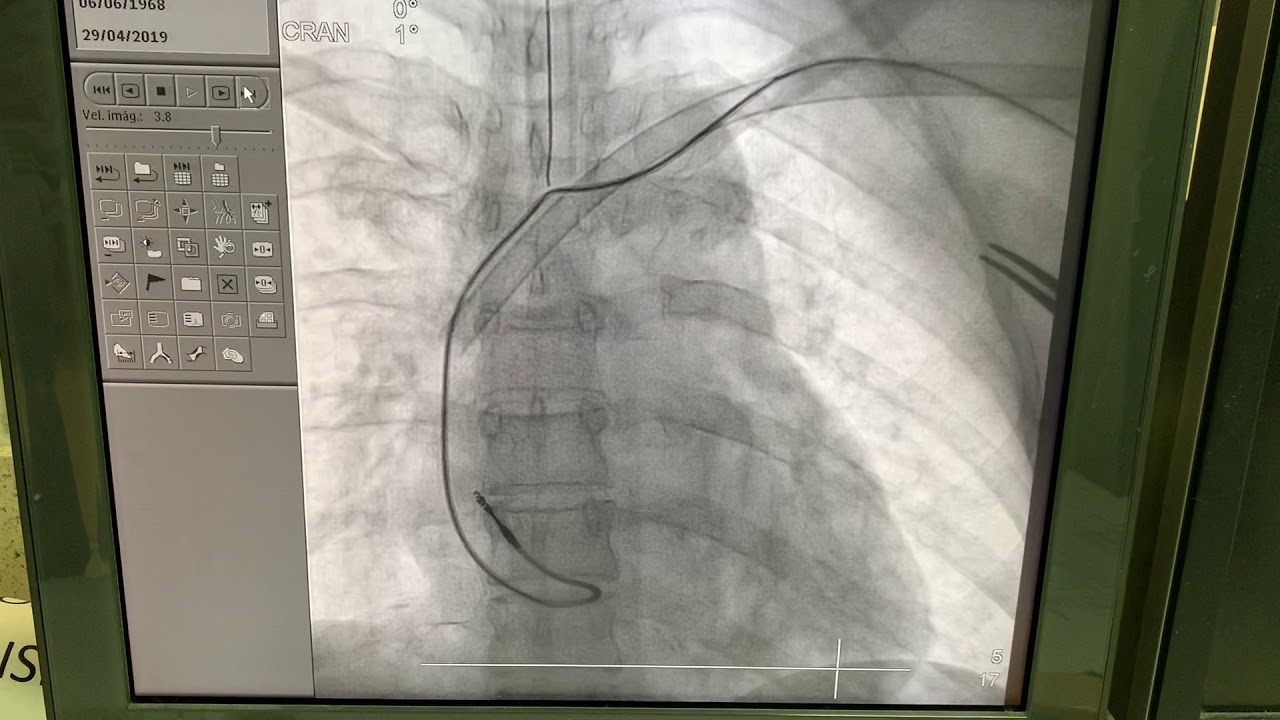

Realicé mi formación como médico general en la Universidad Autónoma de Veracruz Villa Rica, posteriormente la especialidad en medicina interna durante dos años en centro medico nacional Adolfo Ruiz Cortinez UMAE 14 en Veracruz, recibiendo en el primer año el reconocimiento por excelencia académica y en el segundo año reconocimiento al mejor promedio de mi generación. Realicé la subespecialidad en Cardiología clínica en el Centro Médico Nacional “La Raza”, en la Ciudad de México siendo jefe de residentes en el último año de la residencia médica, durante el tiempo la sede recibió el premio a la mejor cede de formadores de cardiología 2012-2013 premio otorgado por Dr. Enrique Graube (en ese entonces Director de medicina UNAM). Entre mis actividades asistenciales y conferencias, he presentado trabajos libres a nivel internacional (congreso de falla cardiaca lisboa 2013, Congreso mundial de cardiologia 2016, 2018 en AHA) ganador del premio internacional “la imagen más bella en cardiología, sociedad europea cardiologia España 2013”, así mismo presentación de más de 35 articulos publicados en revistas indexadas, soy miembro de la sociedad mexicana de cardiología no. 2076, asociación mexicana de cardiología, Fellow in training de la American collegue of cardiology capítulo México. Miembro de la sociedad europea de cardiología ESC ID 509395. Médico adscrito en el centro médico nacional la Raza, fui profesor adjunto del curso de cardiología en el mismo centro y sindal en el exámen de certificación de cardiología clínica de la sociedad mexicana de cardiología. Desde el 2016-2018 realicé curso de alta especialidad en electrofisiología cardiaca y estimulación cardiaca , realizando cursos fuera del país para especialización en técnicas avanzadas de ablación de arritmias, actualmente me encuentro realizando en el segundo año de la maestría en Dirección y Gestión de Instituciones de salud y Especialidad en Gestión de la Salud y Bienestar Corporativo